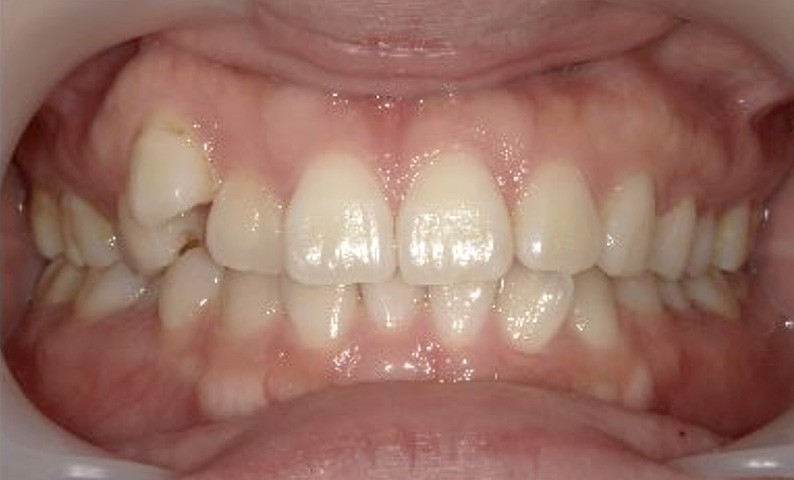

症例_024 上顎だけの部分矯正

治療期間:7ヶ月金額:30万円+税女性前歯のガタガタ上の前歯だけ

| Before | After |